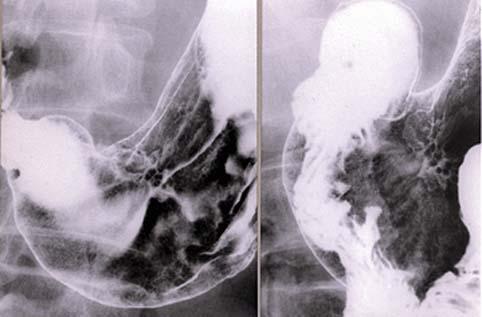

Criteria of Hist.ClassificationMalignant epithelial tumor/Adenocarcinoma

LocationStomach/Angle

Technique, MethodX-ray

Macroscopic TypesType 0/IIc (IIc) Superficial depressed type

Size25 - 29

Depth of Tumor Invasionmucosa